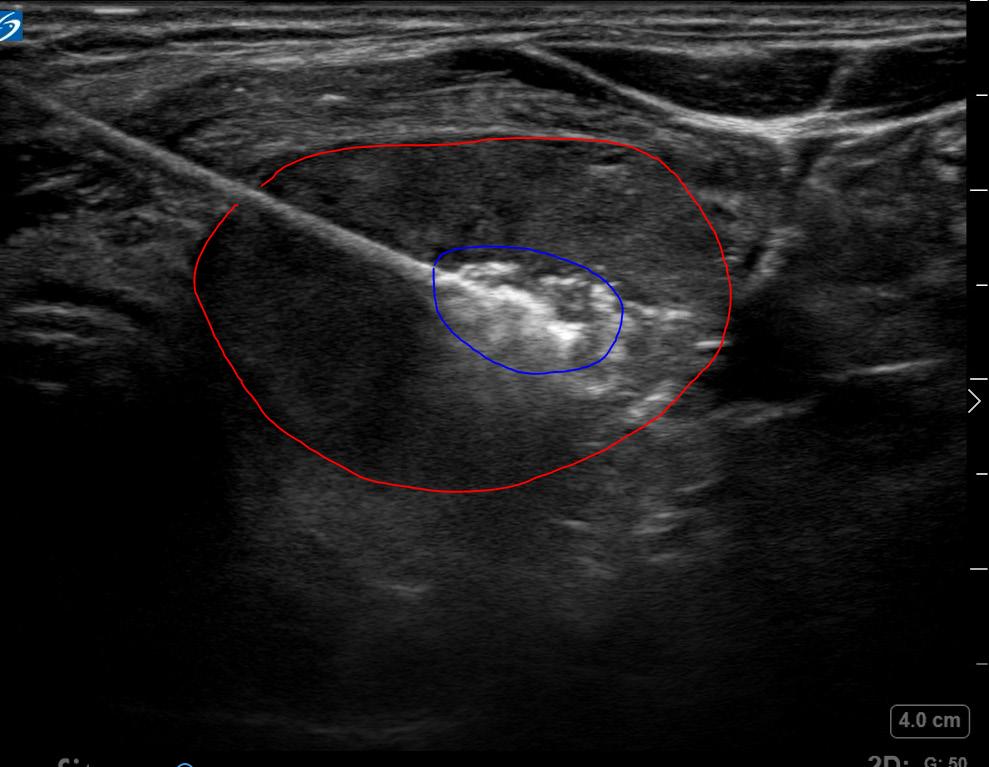

Once the perithyroidal block was completed, the RFA electrode (the size equivalent of an 18-gauge needle) was inserted using ultrasound guidance into the known dominant toxic nodule on the left. Utilizing a transisthmic approach and the “moving shot” technique, I sequentially ablated the dominant left-sided nodule. A maximum of 40 watts was used via a 7 mm active tip electrode, with a total ablation time of about 20 minutes.

I monitored each segment of ablated nodule for hyperechoic “bubbling” visible on ultrasound, and for rising impedance from the electrode generator, to assure adequate ablation throughout. During the critical portion of the procedure, I asked the patient to vocalize to assure that no acute voice changes or hoarseness was observed. None were noted and the patient tolerated the procedure well. A bandage was placed over the needle site and the patient was observed for one hour prior to discharge home. Follow-up was arranged for set intervals (one, three, six and 12 months following the ablation) with ultrasound examination of the nodule and thyroid function lab testing.

Just a few months following the procedure, the patient had completely normal thyroid function restored and is doing very well. Her TSH returned to the normal range following the procedure (1.08)

and she reports that her hyperthyroid symptoms resolved. She feels like the nodule is reducing in size with less compression symptoms in her neck, and she has a more normal neck contour. Volumetric ultrasound analysis of her treated nodule at six months shows that her nodule is now less than 3 mL in volume, a 75% decrease in volume from pre-procedure baseline. Further, the procedure did not cause hypothyroidism necessitating thyroid hormone replacement, a known complication of both surgery and radioactive iodine.